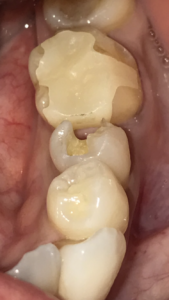

どこを治したかわかりますでしょうか?

おそらく多くの人は第一大臼歯のセラミック修復部分を指すでしょう。

第一大臼歯にはジルコニアインレー(他院による修復)が装着されています。

しかし、私が治療したのはその手前の第二大臼歯です。

銀歯を外し、虫歯をとった時の写真です。欠損した部分のみをダイレクトボンディングにて修復しました。